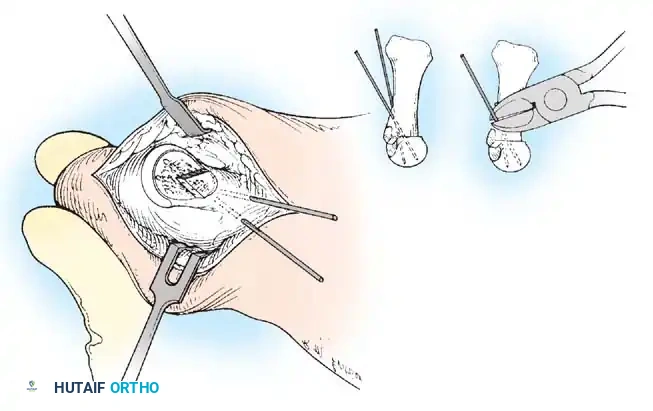

FIBULAR (LATERAL) SESAMOIDECTOMY: DORSAL APPROACH

• If after complete adductor hallucis release and preferably after a lateral capsular release, a fi bular sesamoidectomy is needed to correct the valgus deformity of the great toe fully, it should be done at this time.

• Adequately separate the fi rst and second metatarsal heads for exposure.

• Plantar fl ex the metatarsophalangeal joint 10 to 20 degrees, which reduces tension on the sesamoids.

• Grasp the fi bular sesamoid with a small Kocher clamp or sturdy tissue forceps, and pull it laterally into the intermetatarsal space (Fig. 78-20).

• Release the intersesamoid ligament. When this ligament has been incised, bring the fi bular sesamoid into the intermetatarsal space, where its removal is straightforward. Care must be taken when incising the intersesamoid ligament to avoid severing the fl exor hallucis longus tendon immediately plantar to it. If the tendon is severed, it probably should not be repaired at this level; loss of the tendon causes little if any functional impairment, and

Fig. 78-20 Modifi ed McBride procedure. Fibular sesamoid is removed.

FIBULAR SESAMOIDECTOMY: PLANTAR APPROACH

• If a plantar approach (Fig. 78-21A) is chosen for fi bular sesamoidectomy, have an assistant hold the ankle dorsifl exed, and use a headlight for seeing into the full depth of the wound. Avoid the fl exor hallucis longus tendon and the neurovascular bundle to the fi rst web space.

• Flex and extend the hallux, and inspect the radiograph to locate the sesamoid. Beginning 1 to 1.5 cm distal to the metatarsophalangeal joint, make a longitudinal incision in the plantar surface of the foot, extending the incision proximally 3.5 to 4 cm between the fi rst and second metatarsals.

• If the fi bular sesamoid requires excision, it usually is subluxed.

• When the skin and fascial septa within the forefoot pad have been separated, insert a small self-retaining retractor.

• Using small, blunt-tip dissecting scissors, identify the neurovascular bundle to the fi rst web space, and retract it laterally or medially, depending on the position of the sesamoid (Fig. 78-21B).

• Palpate the sesamoids, and fl ex and extend the hallux to locate the fl exor hallucis longus tendon.

• Open the pulley over the fl exor hallucis longus tendon, and retract the tendon medially. This maneuver is made easier by having an assistant hold the foot in dorsifl exion at the arch with one hand and fl ex the metatarsophalangeal joint to relax the fl exor hallucis longus tendon with the opposite hand.

• At this point, the intersesamoid ligament should come into view; divide it completely (Fig. 78-21C). This may require moving the scalpel 1 or 2 mm laterally or medially to fi nd the groove between the sesamoids.

• Incise the cleavage plane between the two sesamoids, while retracting the fl exor hallucis longus muscle medially and the neurovascular bundle laterally.

• Grasp the fi bular sesamoid with a strong pick-up or small Kocher clamp, and remove the lateral head insertion of the fl exor hallucis brevis muscle on the proximal end of the sesamoid using direct vision (loupe magnifi cation makes this easier, but is not necessary).

• When the medial and proximal restraints of the sesamoid have been released, sever the attachment of the adductor hallucis muscle to its lateral distal edge close to the bone with a scalpel or scissors.

• Sever the last attachment of the sesamoid distally where the plantar plate continues its distal insertion into the proximal phalanx (Fig. 78-21D).

• When the sesamoid has been removed, inspect the wound carefully for any bleeding. Pressing on the edges of the wound helps identify any potential bleeding vessels, which should be cauterized.

• Excising the sesamoid does not release the adductor insertion on the base of the proximal phalanx. This can be released through the plantar incision. Continuing to retract the neurovascular bundle laterally and the fl exor hallucis longus muscle medially, and adducting the hallux, while the opposite index fi nger palpates the adductor, helps identify the structure (Fig. 78-21E).

• Using right-angle retractors, expose the adductor, excise a small section of the tendon, and move the hallux medially.

• At the conclusion of this procedure, the surgeon should be unable to palpate any restraining structures on the fi bular side of the metatarsophalangeal joint. The transverse natatory fi bers in the dorsal aspect of the web space should be released manually. All restraints pulling the hallux laterally (except the extrinsic tendons) must be removed.

• Inspect the neurovascular bundle and the fl exor hallucis longus tendon.*

Fig. 78-21 Fibular sesamoidectomy (plantar approach). A, Incision. B, Common digital nerve to fi rst web space.